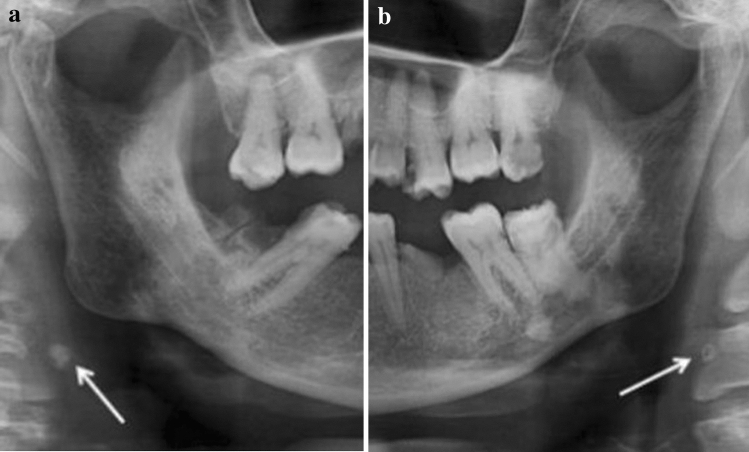

a, b Bilateral carotid artery calcifications at the level of the third cervical vertebra. Superior horn of thyroid cartilage and triticeous cartilage observable at the level of the fourth cervical vertebra

Fig. 7.

a, b Well defined, bilateral nodular radiopacities were seen at the level of the lower margin of the third and the fourth cervical vertebra (C3 & C4). Based on the radiographic location and appearance of the lesion on the radiograph, a provisional diagnosis of the coronary artery calcification was made

The prevalence of bilateral CAC was significantly higher than the prevalence of CAC on the right and the left side, for both male and female patients Fig. 1.

Fig. 1.

Bilateral carotid artery calcifications at the level of the third cervical vertebra. Superior horn of thyroid cartilage and triticeous cartilage observable at the level of the fourth cervical vertebra